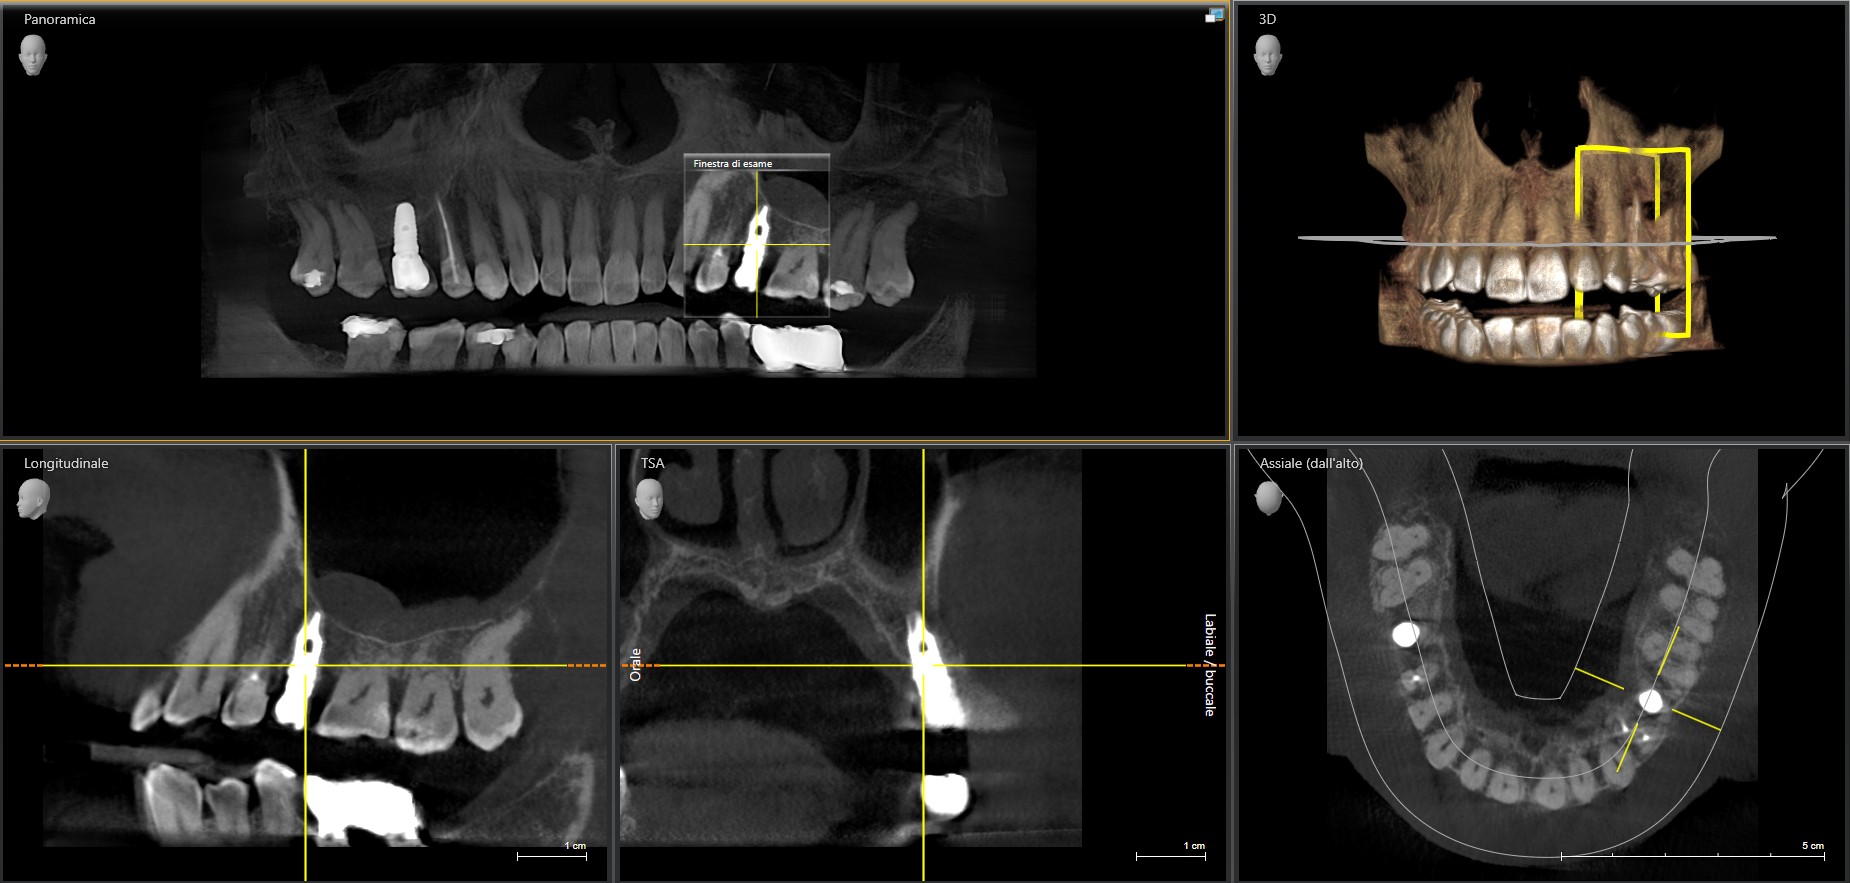

TAC Odontoiatrica Cone Beam (CBCT): Diagnosi Precisa e Trattamenti Personalizzati

Nel nostro studio, ci avvaliamo della TAC odontoiatrica Cone Beam, una tecnologia diagnostica avanzata che permette di ottenere immagini tridimensionali dettagliate delle arcate dentarie e delle strutture ossee circostanti. Questo esame offre una visione completa del cavo orale, migliorando la precisione diagnostica e la pianificazione dei trattamenti.

La TAC Cone Beam utilizza un fascio di raggi X a forma conica per acquisire immagini volumetriche in 3D. A differenza delle radiografie tradizionali, che forniscono immagini bidimensionali, la Cone Beam consente di visualizzare dettagli complessi del cavo orale da ogni angolazione, offrendo informazioni fondamentali per trattamenti personalizzati.

L’utilizzo della TAC Cone Beam nel nostro studio comporta numerosi vantaggi: